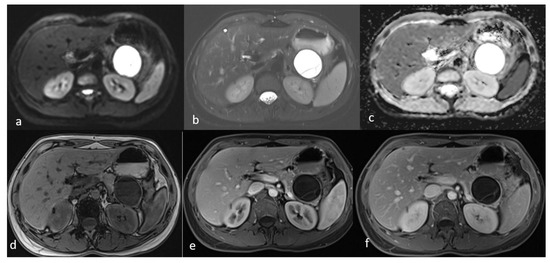

An MRI of the abdomen, performed approximately one year prior to admission, revealed a cystic thin-walled formation with internal septa, located in the dorsal part of the tail of the pancreas. The lesion measured approximately 3.9 cm in diameter and exerted pressure between the pancreas and the greater curvature of the stomach. The walls and internal diaphragms of the cyst showed enhancement post-contrast injection. There was no evidence of pancreatic duct dilation. Differential diagnoses at this stage included pancreatic cystic lesions such as cystadenoma, though the patient’s age was considered atypical, as well as other lesions like cystic lymphangioma or replication cysts. Additionally, incidental findings of mild hepatomegaly and a 9.5 mm hemangioma in the eighth hepatic segment were noted, along with small lymph nodes (Figure 2). In the absence of high-risk features or significant symptoms, a watch-and-wait approach with periodic monitoring was deemed appropriate.

Figure 2.

First MRI axial sequences of the upper abdomen. (a) T2 Blade axial sequence showing hyperintensity of the cyst (white arrows). (b,c) DWI and ADC showing no internal restriction of the cystic lesion. (d) T1 Vibe showing a hypointense cystic lesion at the tail of the pancreas. (e,f) T1 Vibe post-contrast at arterial and venous phases showing only minimal enhancement of the cyst wall and the septations with no internal solid component.

An MRI performed one year after the initial imaging and two months before admission revealed an increase in the size of the pancreatic cystic lesion to 4.5 cm (Figure 3 and Figure 4) with enhancement of its thin wall and internal septa, confirming its progressive nature. The lesion continued to compress the pancreatic tail and the greater curvature of the stomach, without causing pancreatic duct dilation. The imaging also showed low signal intensity on T1- and high signal intensity on T2-weighted sequences, with capsule enhancement post-contrast, suggesting a mucinous cystic neoplasm (Figure 4). Additionally, the MRI confirmed the presence of a 9 mm hemangioma and a small liver cyst, both unchanged from prior scans. No enlarged retroperitoneal lymph nodes were observed, and the MRCP findings showed normal intrahepatic bile ducts, common hepatic bile duct, gallbladder, and pancreatic duct. No abnormalities were found in the spleen, kidneys, or adrenal glands.

Figure 3.

(a,b) Axial sequences of the upper abdomen comparison showed an increase in the lesion size.

Figure 4.

Second MRI follow-up after 6 months showed an increase in the lesion size. (a) T2 Blade axial sequence showing hyperintensity of the cyst with no internal solid component. (b,c) DWI and ADC again showing no internal restriction of the cystic lesion. (d) T1 Vibe showing a hypointense cystic lesion at the tail of the pancreas. (e,f) T1 Vibe post-contrast at arterial and venous phases showing no change in the enhancement of the cyst.